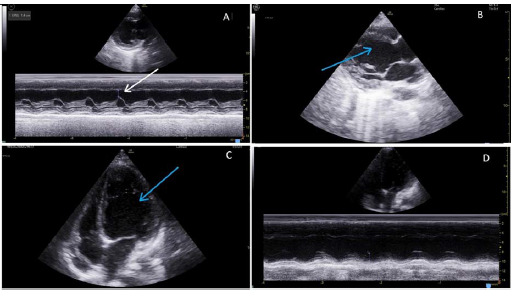

Case presentation: We report the case of a young female patient who presented with multiple episodes of tonic posturing and altered level of consciousness. Diagnostic evaluation revealed severe hypocalcemia with hypomagnesemia, QT prolongation, and episodes of non-sustained ventricular tachycardia. The condition was managed with calcium and magnesium supplementation. Further investigations revealed a novel missense mutation in transient receptor potential melastatin 3 (TRPM3).

Conclusion: The patient was initially misdiagnosed with epilepsy for the past two years. Following a comprehensive evaluation, she was successfully treated with intravenous calcium and magnesium. On follow-up after six months, her condition showed marked improvement, characterized by better cardiac function and the absence of further seizure episodes. This case represents the first reported instance of a TRPM3 mutation affecting calcium channels, highlighting the need for further investigation into its implications for calcium metabolism.